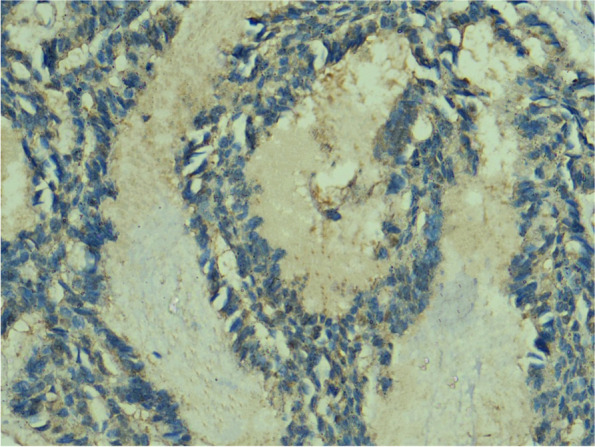

Anti-HCV core antigen expression was absent in all the cases of Canalicular Adenoma (Fig. 2) as well as in cases of Papillary Oncocytic Cystadenoma (Fig. 3). Additionally, 6 out of the 21 Pleomorphic Adenomas showed negative expression (Fig. 4). When the expression of anti-HCV core antigen was examined in different types of malignant SGNs, Adenoid Cystic Carcinoma was the only case out of the 16 that showed negative expression (Fig. 5).

Fig. 4.

Photomicrograph showing negative HCV core antigen expression in a case of Pleomorphic Adenoma, magnification 400x